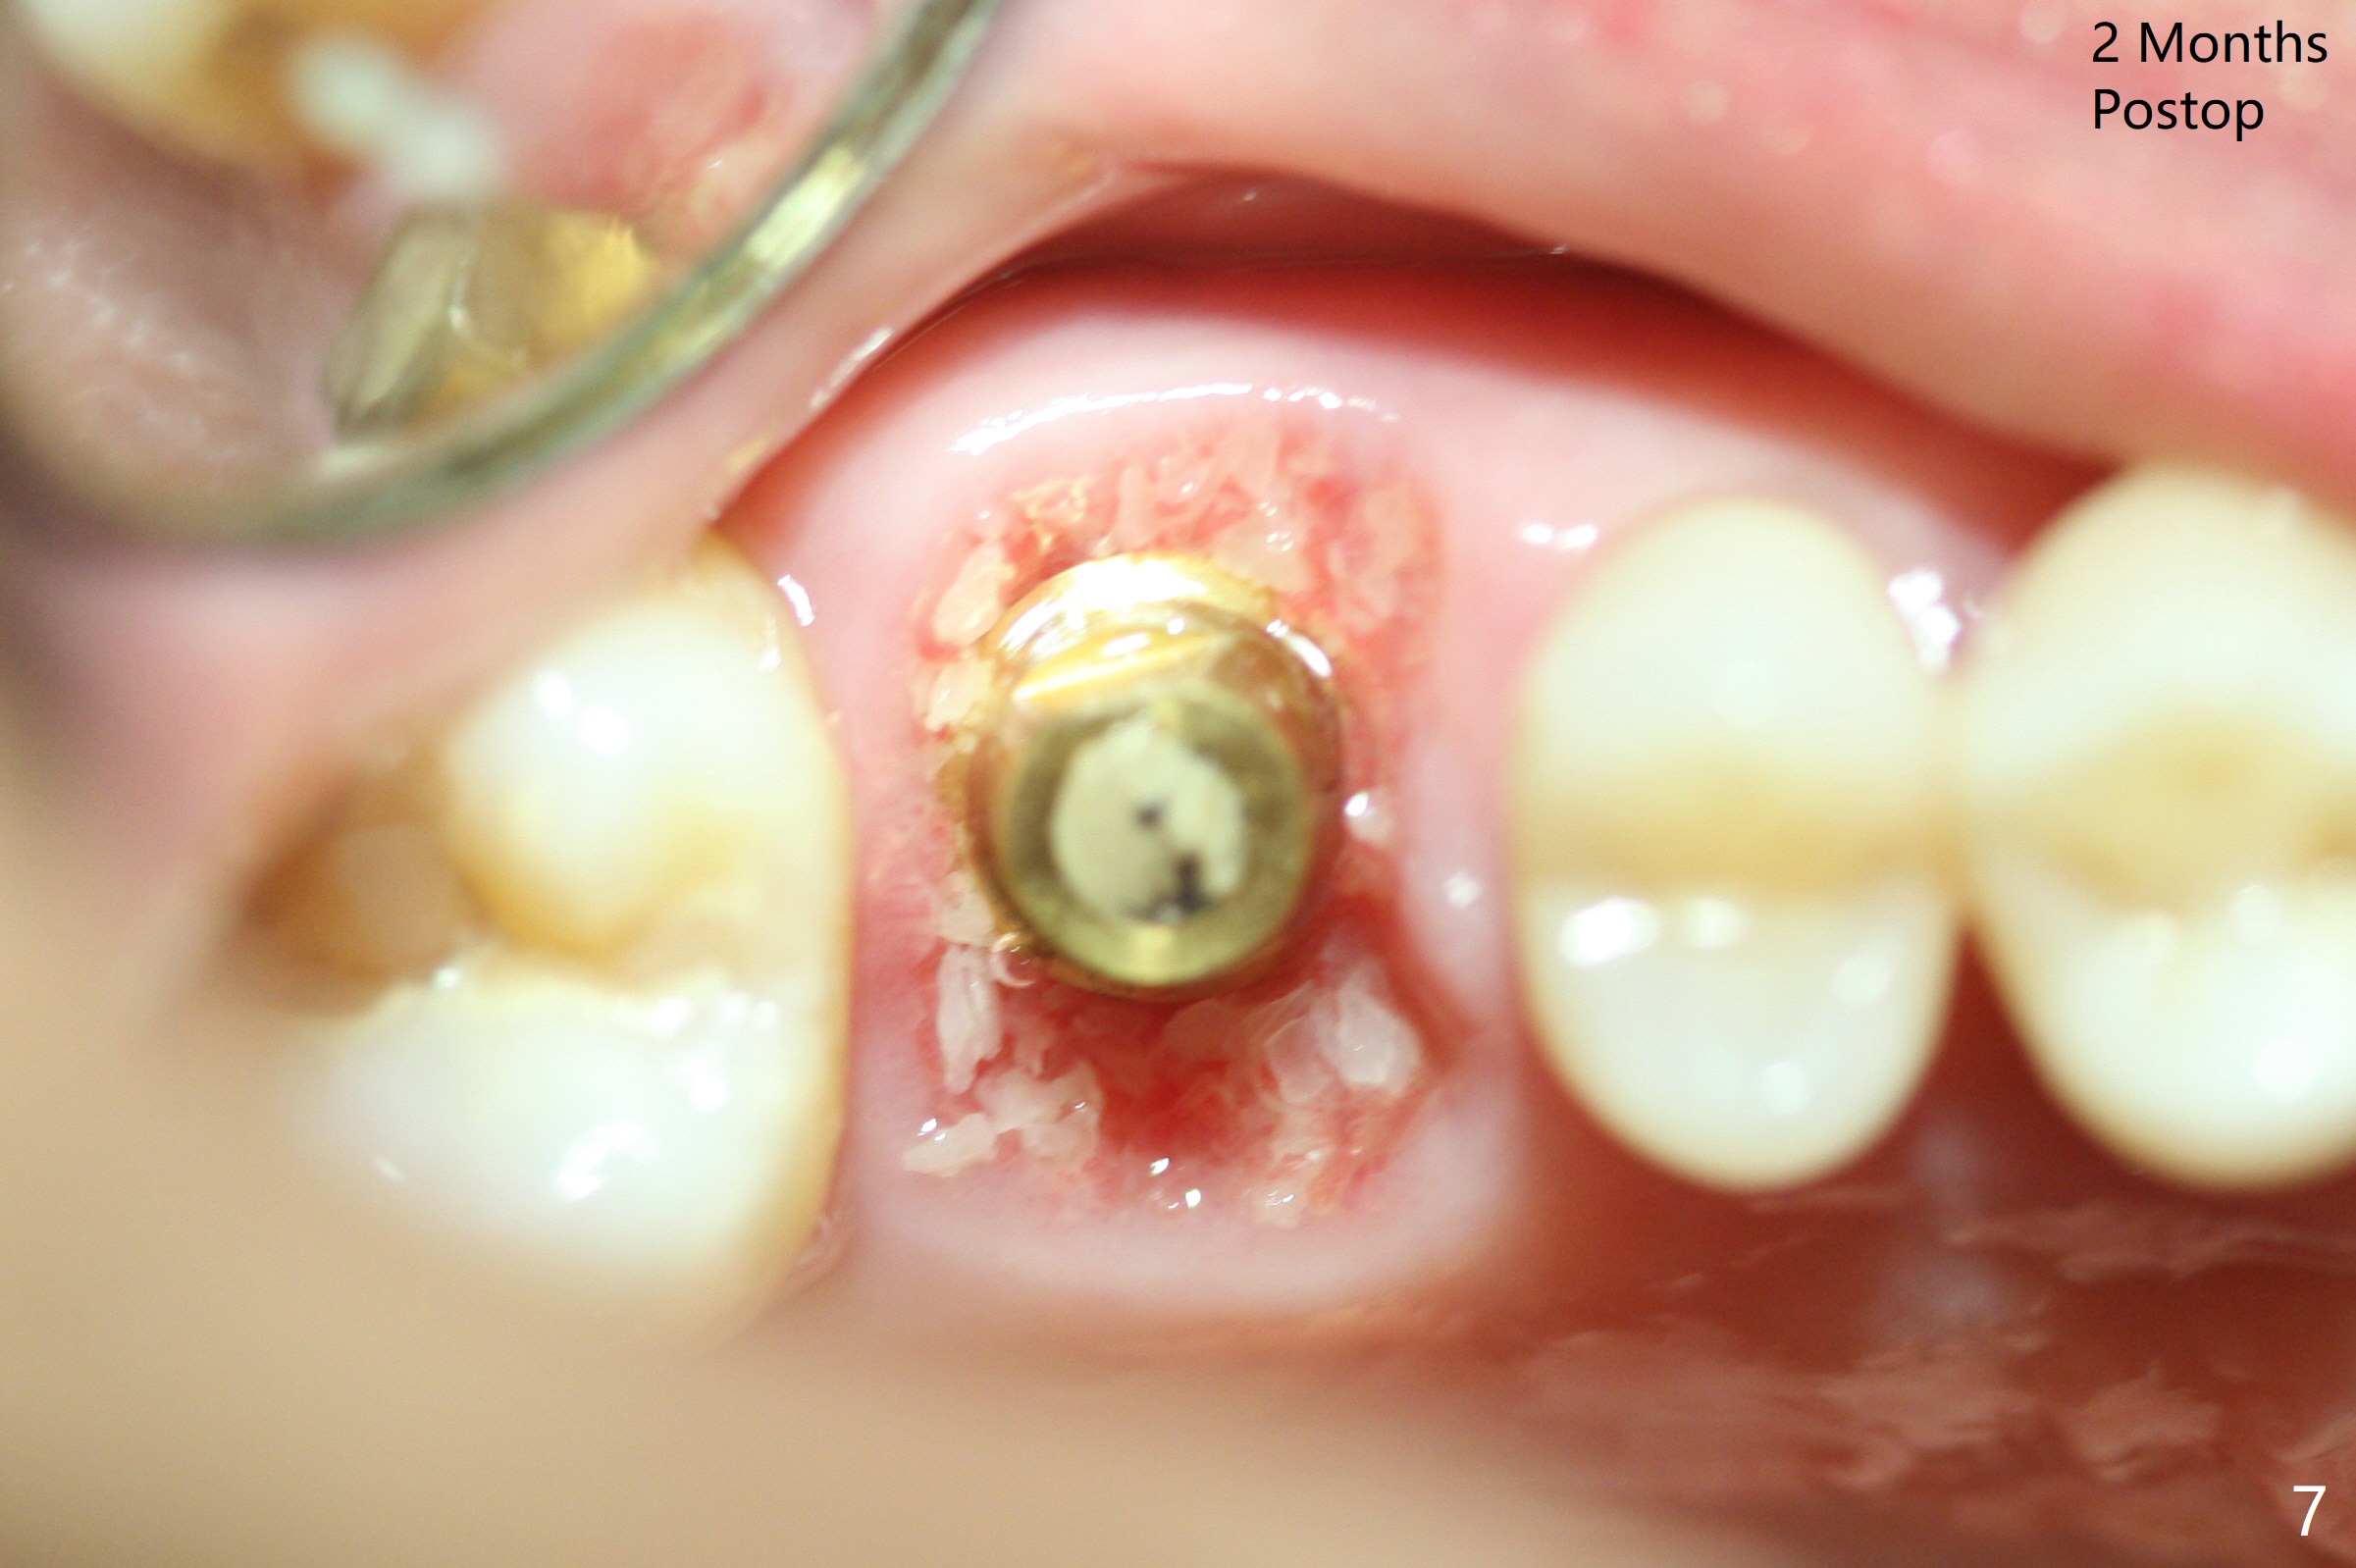

While the tooth #3 has a mesiodistal crack line, etiology may be due to chronic periodontitis with bruxism. After extraction, there is granulation tissue attached to the distobuccal (DB) root. The DB socket is larger than the mesiobuccal one (Fig.1). Osteotomy is initiated in the DB slope of the septum for 10 mm (Fig.2,3). Since there is ample apical bone, the depth of the osteotomy increases to 11.5 mm. When a 5x10 mm dummy implant is placed, primary stability is satisfactory (Fig.4 (yellow line: apical space)). The definitive implant remains the same dimension with deeper placement (Fig.5,6 (~ 20 Ncm)); with placement of a 6.5x4(3) mm abutment and Vanilla/Osteogen Graft (*), an immediate provisional is fabricated in place (without taking out for trimming) with sufficient clearance with the opposing dentition. It appears that the moderately long implant (10 mm) is able to achieve primary stability for immediate placement. When the provisional is removed 2 months postop, bone graft seems to be adhered to the socket (Fig.7). To improve local hygiene, the provisional does not return. The implant seems to have osteointegrated 3.5 months postop (Fig.8). The crown/abutment is loose approximately 1 year post cementation. Due to her daughter's contracting COVID 19, she postpones returning for approximately 1 year. The access hole is opened, crown/abutment (6.5x4(4) mm) removed, proximal contacts reduced, crown/abutment reseated without certainty. BW shows incomplete seating probably due to bony interference (Fig.9). A 5.5x4(4) mm can not be seated (bouncing, probably due to soft tissue interference). When a 4.5x5(4) mm abutment (UF) is seated, hand tightening is smooth, confirmed by BW (Fig.10). Two weeks later, the new crown is cemented intraorally. The crown/abutment is removed for cleaning. The abutment screw is torqued at 20 NCM.